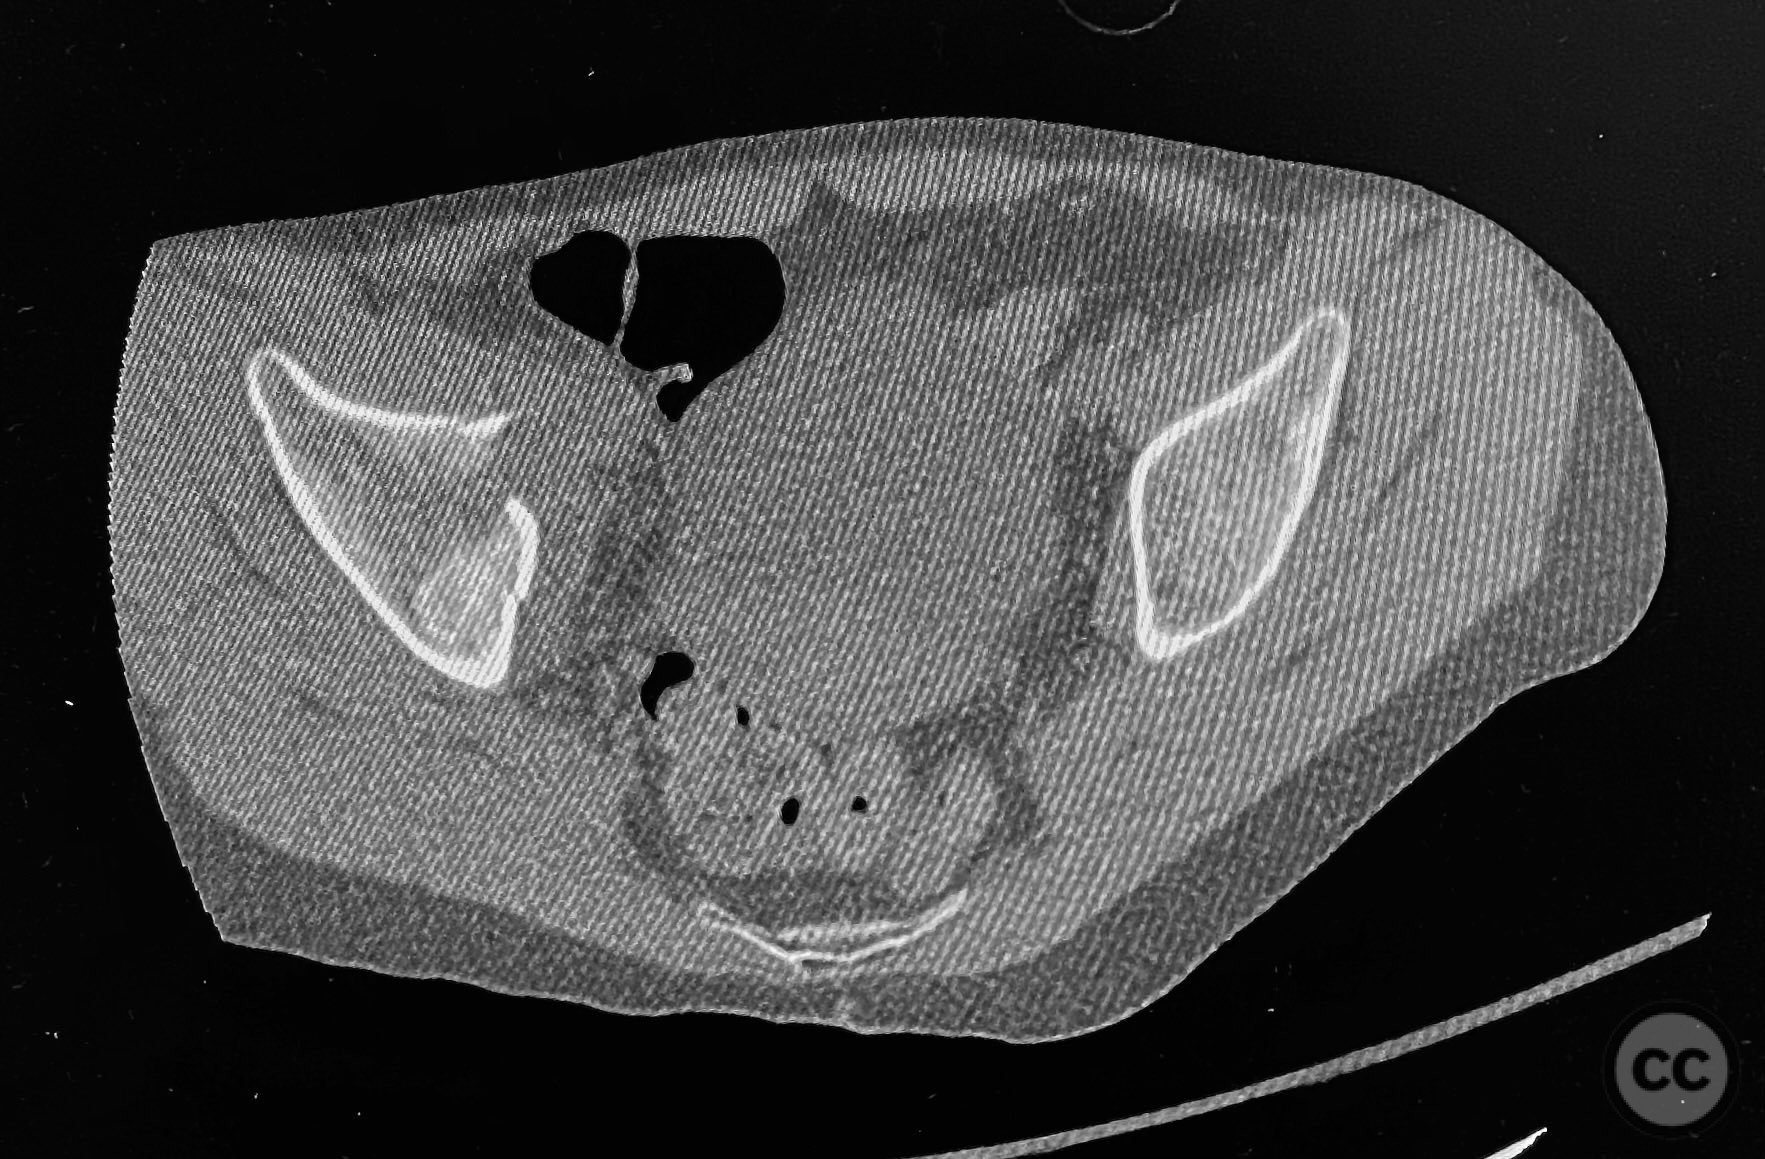

Clinical and radiological findings:  The patient sustained an acetabular fracture with a rare posterior medial dome impaction fragment, as demonstrated on AP pelvic radiographs obtained in skeletal traction. Surface renderings and axial CT images revealed multiple incomplete fracture lines, including a rhomboid-shaped cortical fragment adjacent and proximal to the anterior column/wall fragment. Coronal and sagittal reconstructions further delineated the impacted articular fragment and its relationship to the surrounding acetabular dome. The fracture pattern is classified as AO/OTA 62B3 (associated both-column fracture with dome impaction).